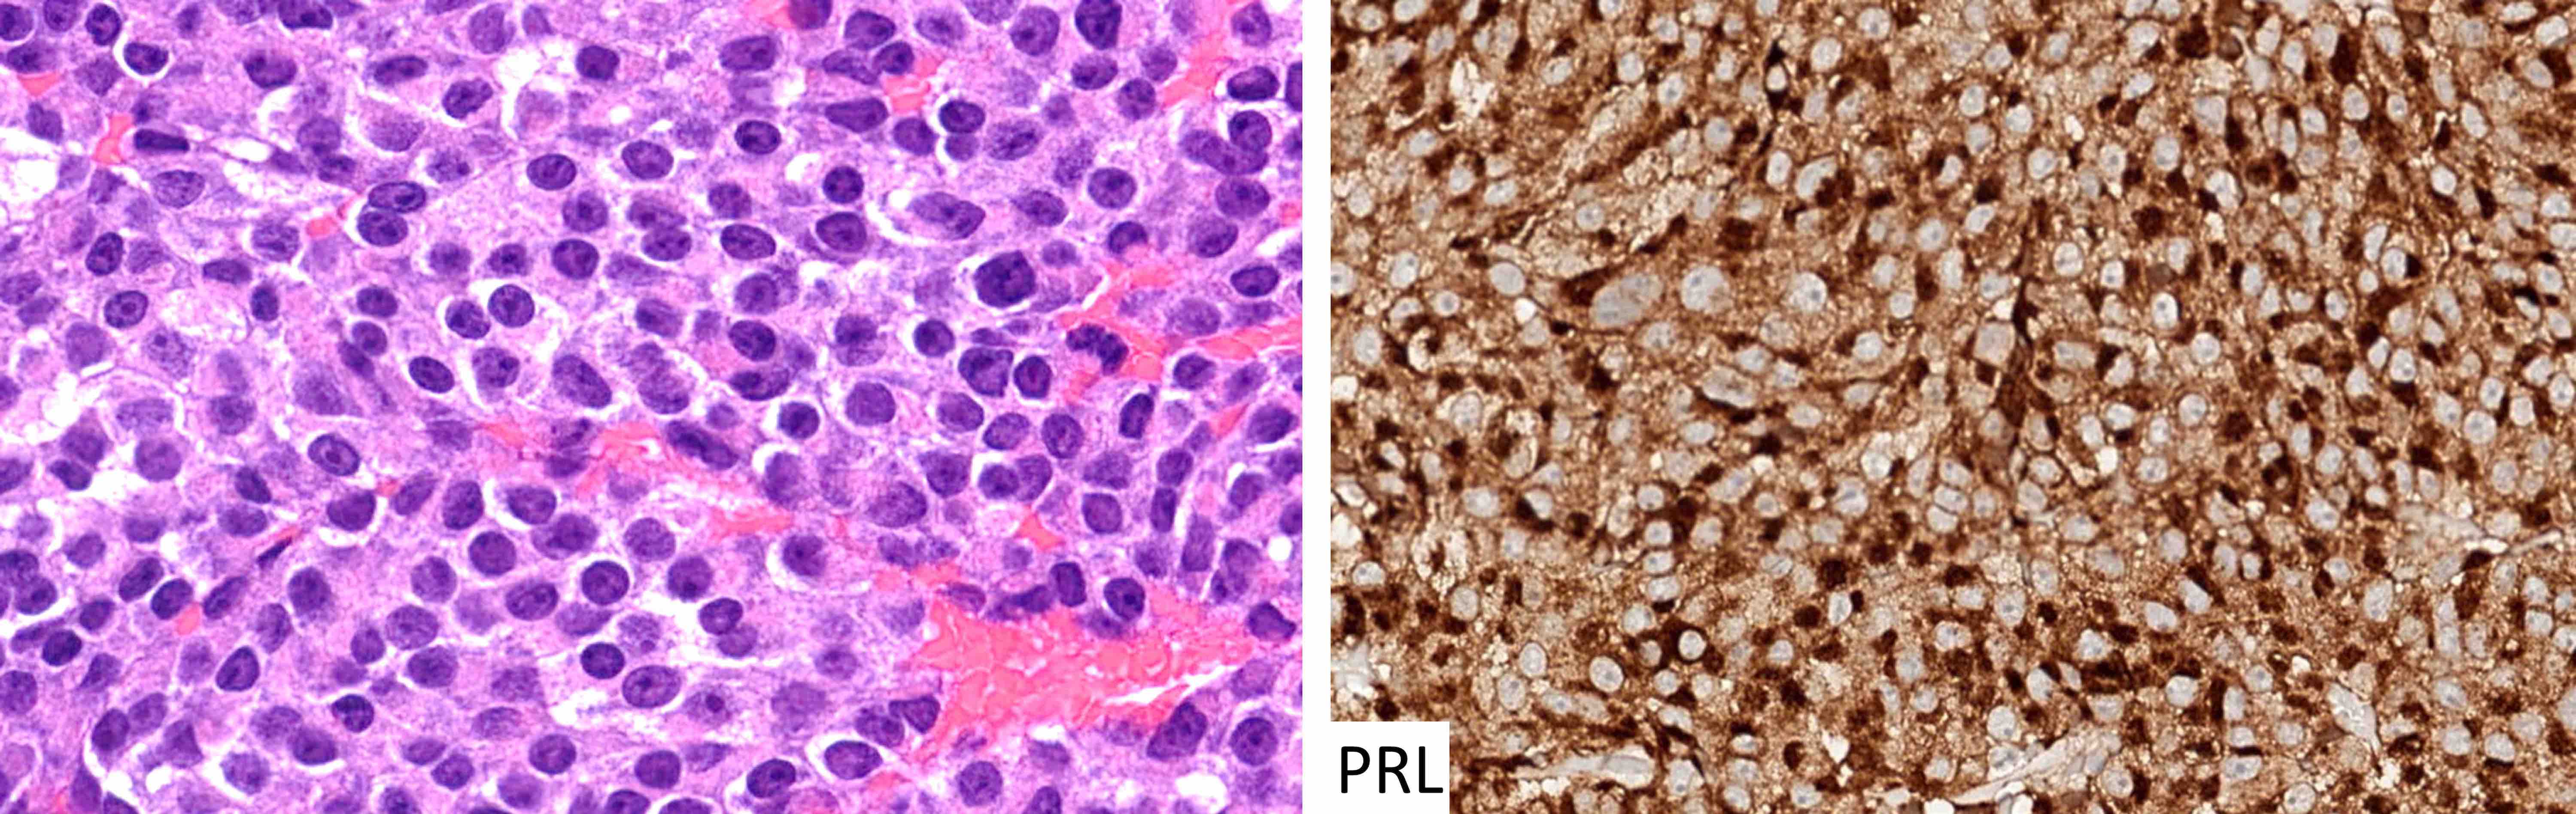

Contributed by Sylvia L. Asa, M.D., Ph.D.

| Sparsely granulated lactotroph tumor | Pit1, ER | PRL (juxtanuclear) | Variable keratins | Hyperprolactinemia (tumor size correlates with PRL level) |

| Densely granulated lactotroph tumor | Pit1, ER | PRL | Variable keratins | Hyperprolactinemia |

| Acidophil stem cell tumor | Pit1, ER | PRL with or without GH (weak, focal) | Variable keratins with or without fibrous bodies | Hyperprolactinemia |

- Dopamine agonists can reduce prolactin levels and the size of sparsely granulated lactotroph tumors

- Stains for pituitary transcription factors (Pit1, Tpit, SF1, ER and GATA3) and hormones provide the basis for tumor classification (see Diagrams / tables)